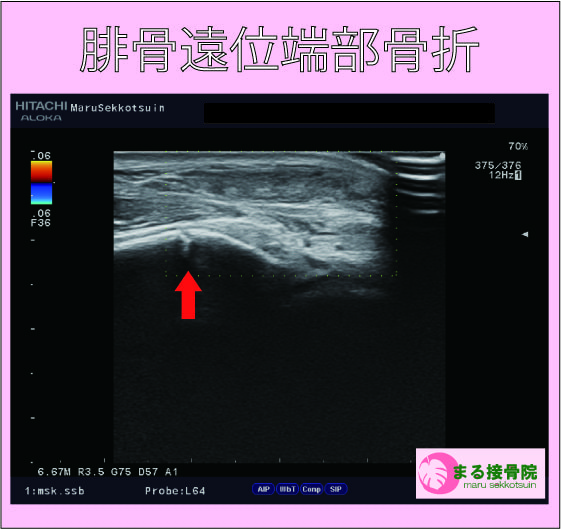

しっかり受傷機転、状況をお聞きしてからエコー検査。

結果、外くるぶしの骨折「腓骨遠位端部骨折」でした。

外くるぶしの骨折は、足首を内返しに捻挫した時に、たまに起こる骨折でして、子供から大人まで起こりうる骨折です。

お子さんの腓骨遠位端(外くるぶし)の骨折は、外くるぶし付近に骨端線といって、成長軟骨部分があり、しっかりと固定、処置、荷重時期のコントロールを行わないと、成長障害を起す場合もあるので注意が必要です。